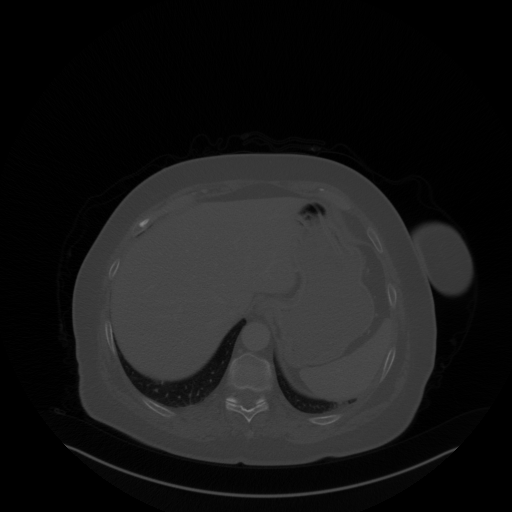

Original VENOUS CT scan

Full window (WL 1023.5, WW 4095 β†’ Low βˆ’1024, High +3071)

Lung window (WL -600, WW 1500 β†’ Low βˆ’1350, High +150)

Mediastinum window (WL 40, WW 400 β†’ Low βˆ’160, High +240)